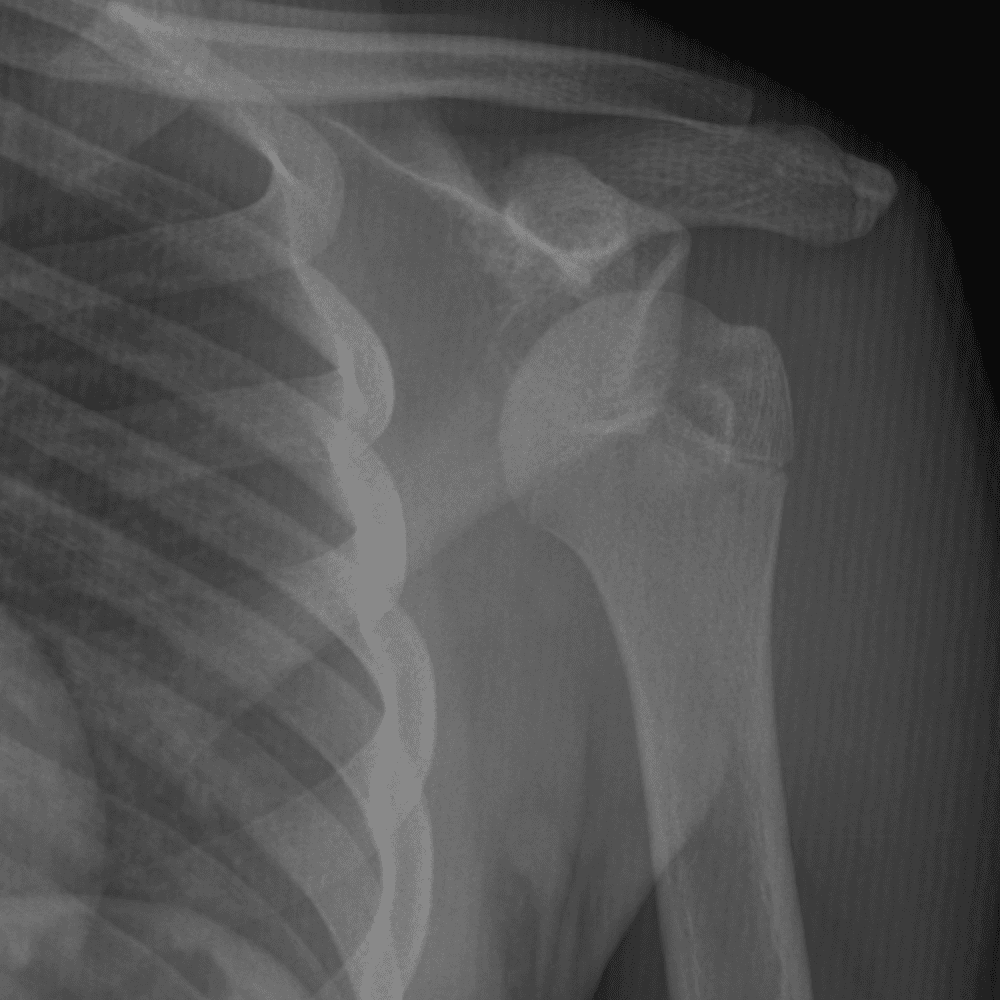

Simuliert den Dienst durch subtile oder schwierige Fälle und einige Normalbefunde.

30 Fälle